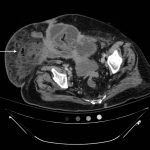

Significant findings:

Computed tomography (CT) of the abdominal and pelvis with intravenous (IV) contrast revealed inflammatory changes, including gas and fluid collections within the ventral abdominal wall extending to the vulva, consistent with a necrotizing soft tissue infection.